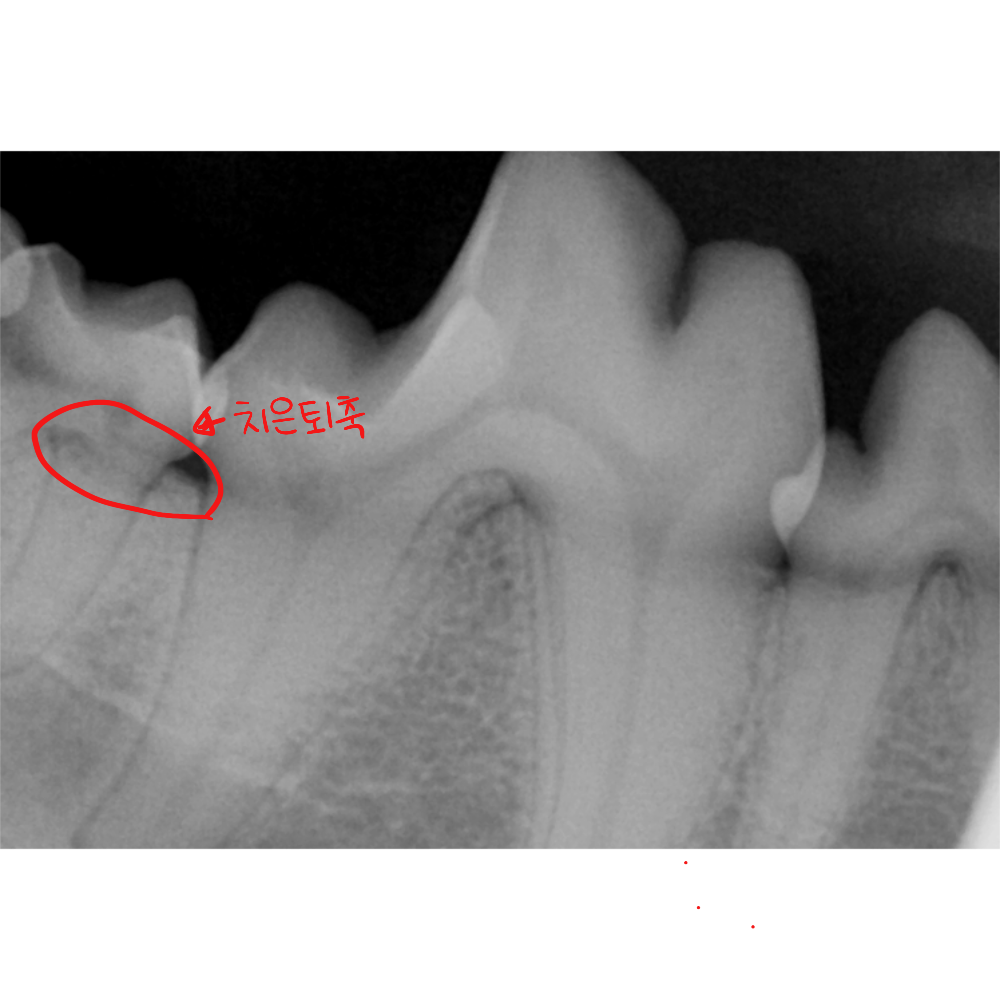

■ 플라크의 석회화: 양치질이 단 하루만 소홀해도 입안의 세균막은 딱딱한 치석으로 변하기 시작합니다. 잇몸 라인을 타고 올라오는 치석은 결국 잇몸을 물리적으로 밀어내며 '치은퇴축'을 일으킵니다.

② 구강 엑스레이를 통한 치조골 분석 (가장 중요!)

겉으로 보이는 잇몸은 '살'에 불과합니다. 진짜 중요한 것은 치아를 잡고 있는 '뼈(치조골)'입니다. 정상 범위: 엑스레이상에서 치조골의 높이가 치근(뿌리)의 상당 부분을 감싸고 있다면 보존이 가능합니다. 발치 대상: 치조골이 녹아내려 치아 뿌리가 절반 이상 드러나고 뼈 사이가 비어 있다면, 이는 통증의 원인이 되므로 발치를 권장합니다.